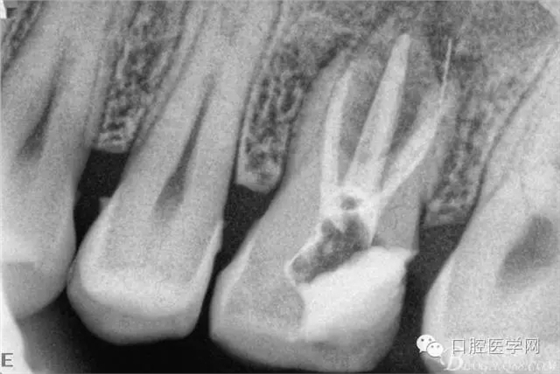

四個(gè)月后患牙Ⅰ°松動(dòng)明顯好轉(zhuǎn),根管內(nèi)無異物,可行根管充填。試主尖片。

根管充填后(遠(yuǎn)頰根內(nèi)有一斷針)。

根充后三個(gè)月。

根充后四個(gè)月。根尖炎性陰影明顯減小,唯獨(dú)遺憾的是遠(yuǎn)頰根一斷針,不知后續(xù)如何,日后再行根尖手術(shù)吧。